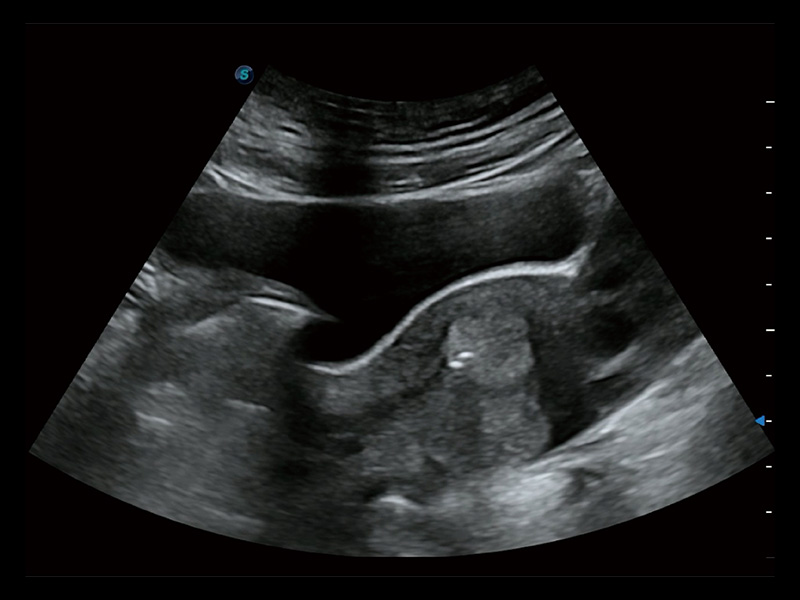

临床图

超声引导下胚胎移植